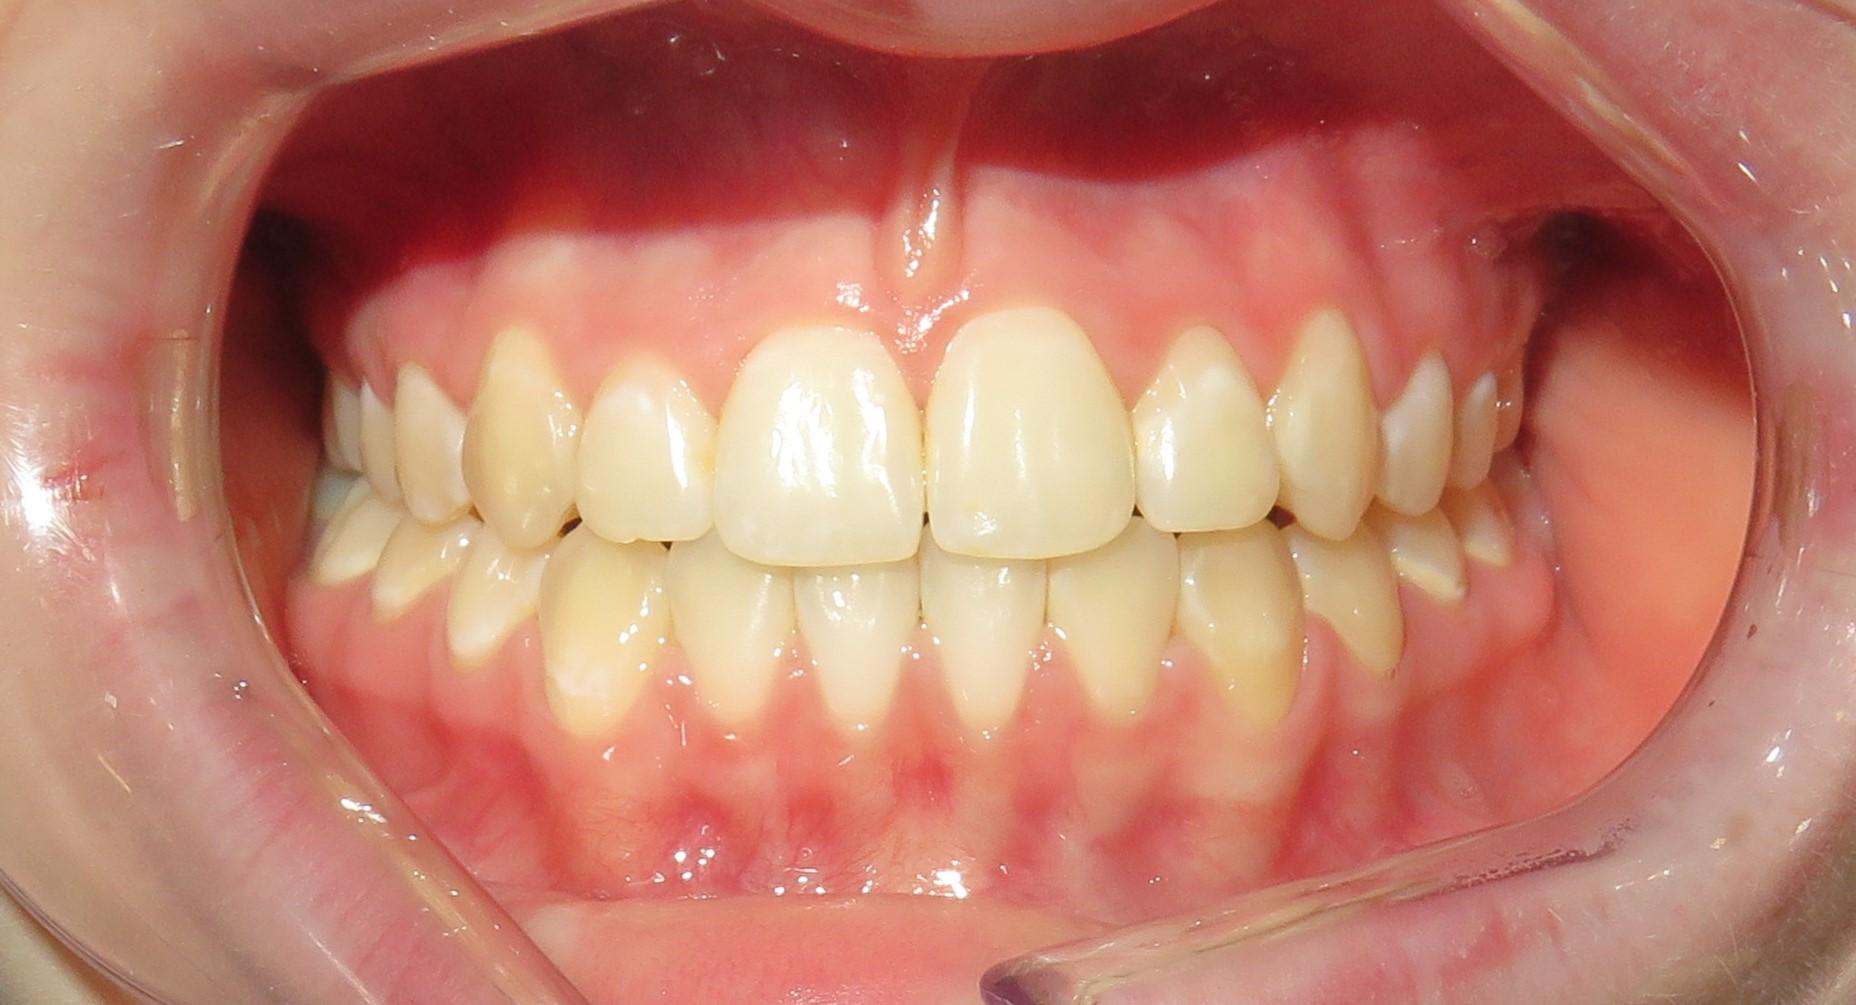

Przedstawiamy metamorfozę naszej Pacjentki, której bardzo zależało na wyprowadzeniu swoich problemów zarówno leczniczo jak i estetycznie.

Pacjentka, zgłaszając się już na kolejną wizytę świadomie podjęła opcję pośrednią z proponowanych działań: wyleczenie zębów zachowawczo, endodontycznie z zabezpieczeniem protetycznym, estetyczne korekty uśmiechu licówkami, ćwierćkoronami i koronami, jednak bez pełnej przebudowy zwarcia (z zachowaniem starszych odbudów w strefach bocznych, które były wykonane na implantach w przeszłości), która jest zawsze najbardziej polecana, odtwarza prawidłowe kontakty, a także umożliwia lekarzowi i technikowi najlepsze warunki do nadania odpowiednich i harmonijnych kształtów. Te wszystkie działania chronią na przyszłość staw skroniowo-żuchwowy.

Następnie dr Joanna przekierowała Pacjentkę na kompleksowe działania endodontyczne do dr Aleksy Muchy.Po tym dr Joanna mogła przystąpić do działań protetycznych.

Prace protetyczne odbywały się we współpracy z Laboratorium Dental Scan, ściślej z Panią Anną Simierską i Agatą Łatyk-Banasik.

Cała terapia, jak zawsze w takich przebudowach, nawet częściowych wiąże się z bezwzględnym zwieńczeniem wykonania szyny ochronnej, której konstrukcja jest zawsze uwarunkowana indywidualnie. Zalecenia jej noszenia przez lekarza również są indywidualne i mogą się zmieniać w perspektywie czasu.

Tak wyprowadzony Pacjent powinien stawiać się (oczywiście zawsze z szyną) na wizytach kontrolnych co 6 m-cy. W międzyczasie z zaleceń lekarza z pewnością wskazane mogą być zabiegi higienizacyjne u naszych Pań higienistek, by podtrzymać u Pacjenta zdrowy stan przyzębia.

Tak Pacjentka skomentowała uzyskany efekt: “Od zawsze marzyłam o takiej zmianie, żałuję, że nie zdecydowałam się wcześniej”.